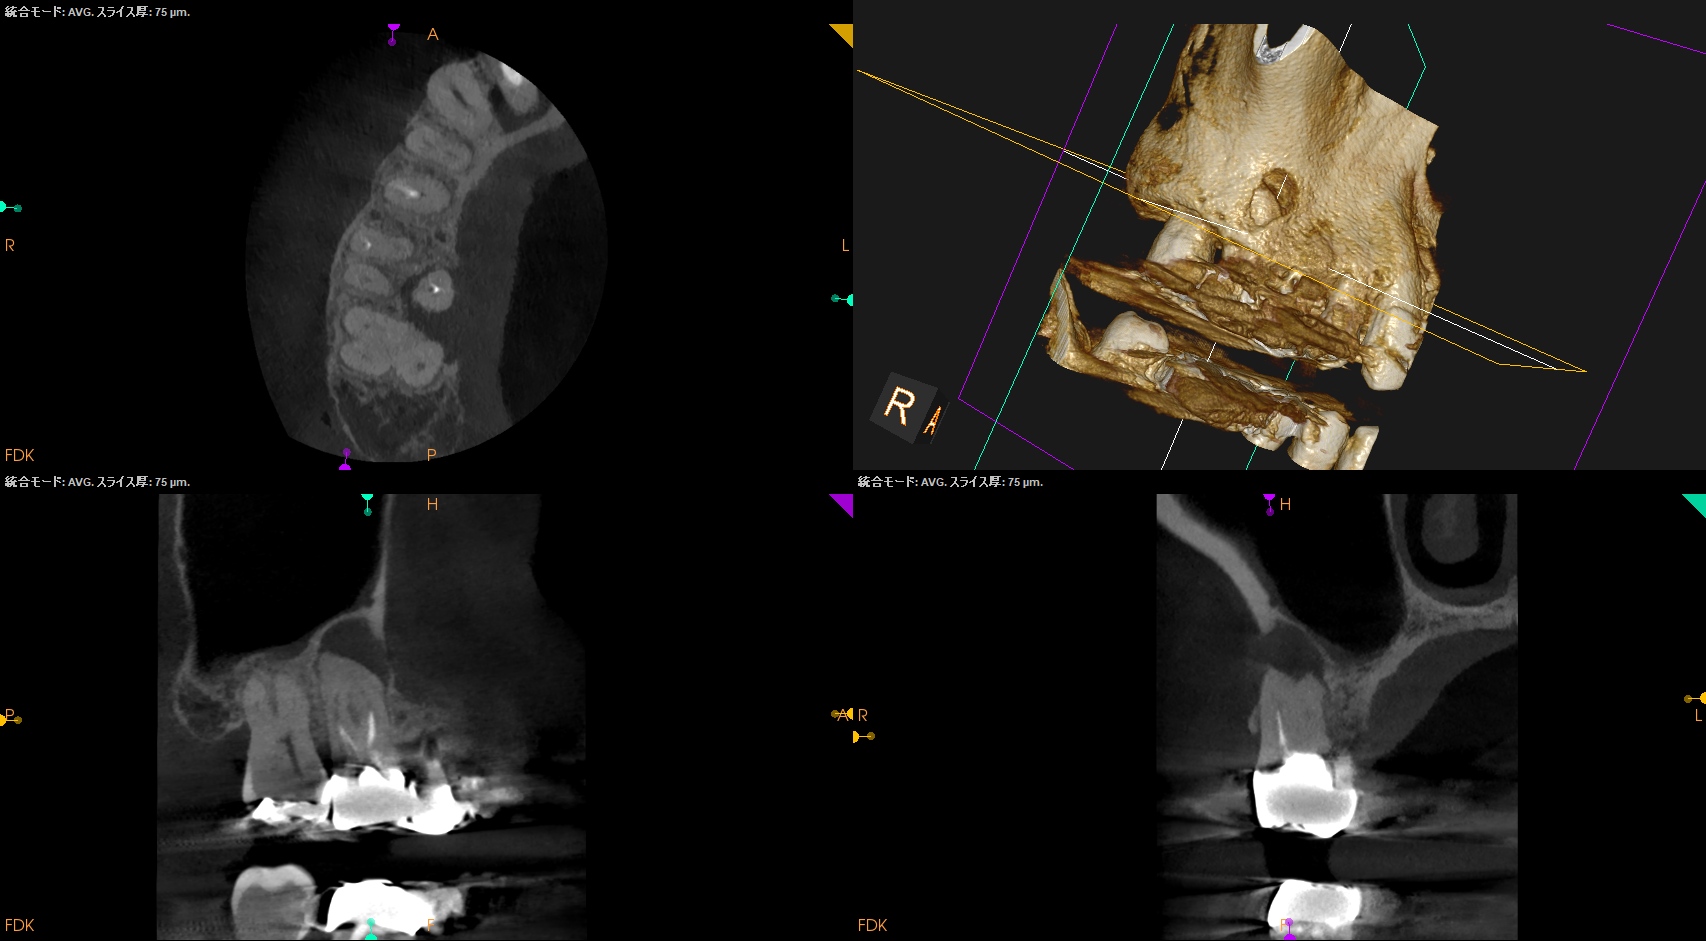

CBCT(2025.9.22)

#4

#3 MB

DB

P

これで抜歯とは…意味がわからない。

このCBCTの絵でこの結果が想像できるだろうか?

このことから何が言えるか?と言えば、

CBCT画像からのみ根尖部の解剖学的形態・状態を推し量るのは無理である

という臨床的事実だ。

再根管治療は実際にFileを根管の中に入れないとそれに意味があるかどうか?はわからないのである。